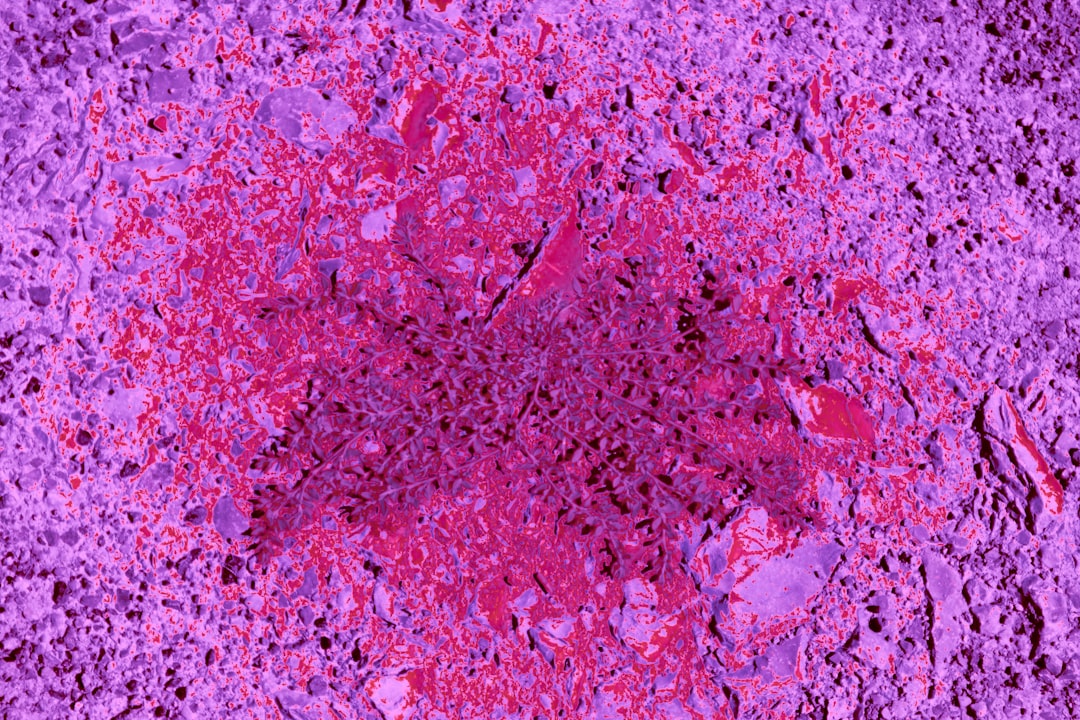

대장암은 우리 몸의 소화기관 중 하나인 대장에서 발생하는 암으로, 조기 발견이 핵심입니다. 대장암 의심 증상? 초기 증상부터 알아보자라는 주제로 이야기해보겠습니다. 대장암이 발생했을 때, 초기에는 뚜렷한 증상이 나타나지 않을 수 있습니다. 하지만 몇 가지 신호를 통해 조기에 발견할 수 있으며, 이를 통해 생존율을 높일 수 있습니다. 이러한 신호는 흔히 무시되기 쉽기 때문에 주의 깊게 살펴보아야 합니다.

대장암 의심 증상으로는 다른 증상들도 다양하게 존재합니다. 이러한 증상들은 보통 대장 내에서의 이상 소견을 바탕으로 합니다. 간혹 대변에 혈액이나 점액이 섞여 나오는 경우가 있는데, 이것은 결코 가벼운 증상이 아닙니다. 실제로 제 주변에서 이러한 증상을 겪었던 지인이 있었는데, 초기 검사로 인해 조기에 대장암이 발견되었습니다. 모두가 이처럼 본인에게 소중한 시간을 소홀히 하지 않도록 하길 바랍니다.